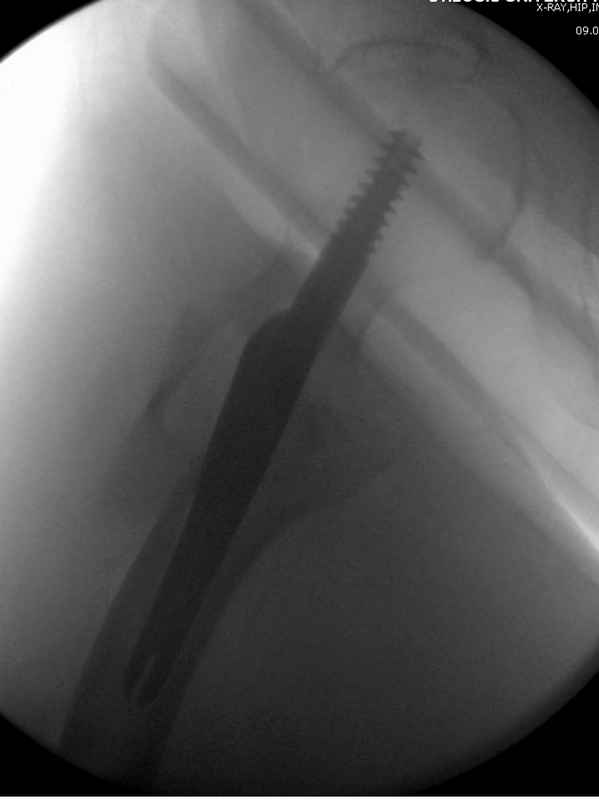

Re: Чрезвертельный перелом бедра

Здесь 83 года, травма в результате падения